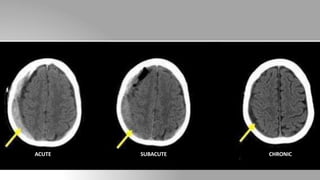

• Appearance of SDH depends upon the time since its formation:

Acute SDH (<3 days): Crescentic, hyperdense

Subacute SDH (3-14 days): Nearly isodense, for detection often CECT

is needed

Chronic SDH (>14 days): Hypodense with enhancing membrane.

ACUTE SUBACUTE CHRONIC

Subdural hemorrhage • Location:Between the dura and arachnoid mater • In contrast to EDH, SDH is not limited by sutures but are limited by dural reflections (falx cerebri, tentorium and falx cerebelli) • Appearance of SDH depends upon the time since its formation: Acute SDH (<3 days): Crescentic, hyperdense Subacute SDH (3-14 days): Nearly isodense, for detection often CECT is needed Chronic SDH (>14 days): Hypodense with enhancing membrane.